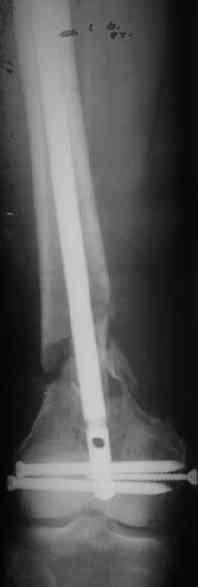

Длину восстановили, возможно, даже с изьбытком, ну да динамизируем пораньше. Введенные в овальное отверстие дистальые винты имеют угловую стабильность. Снимки приложены. Заранее спасибо за критику и комментарии.

Довольно симпатично получилось. Не сомневался, что будет именно такой антеградный реостеосинтез.

Была ли педресация на столе после окончательной фиксации? Уверен ли ты, что "угловая стабильность" дистальных винтов позволит агрессивно заниматься разработкой движений в коленном суставе?

Nicely executed surgery with good planning resulting in great looking x-rays but not the best the way to deal with this fracture. Earlier fracture was having slight translation with no angulation and no instability, now ur fracture is distracted with potential instability as your construct is not the best suited to this place, so more likelihood of non union or complications.

Good luck to you and your patient

Should have preferred a locking plate if at all u wanted to reoperate and

added copious bone graft.